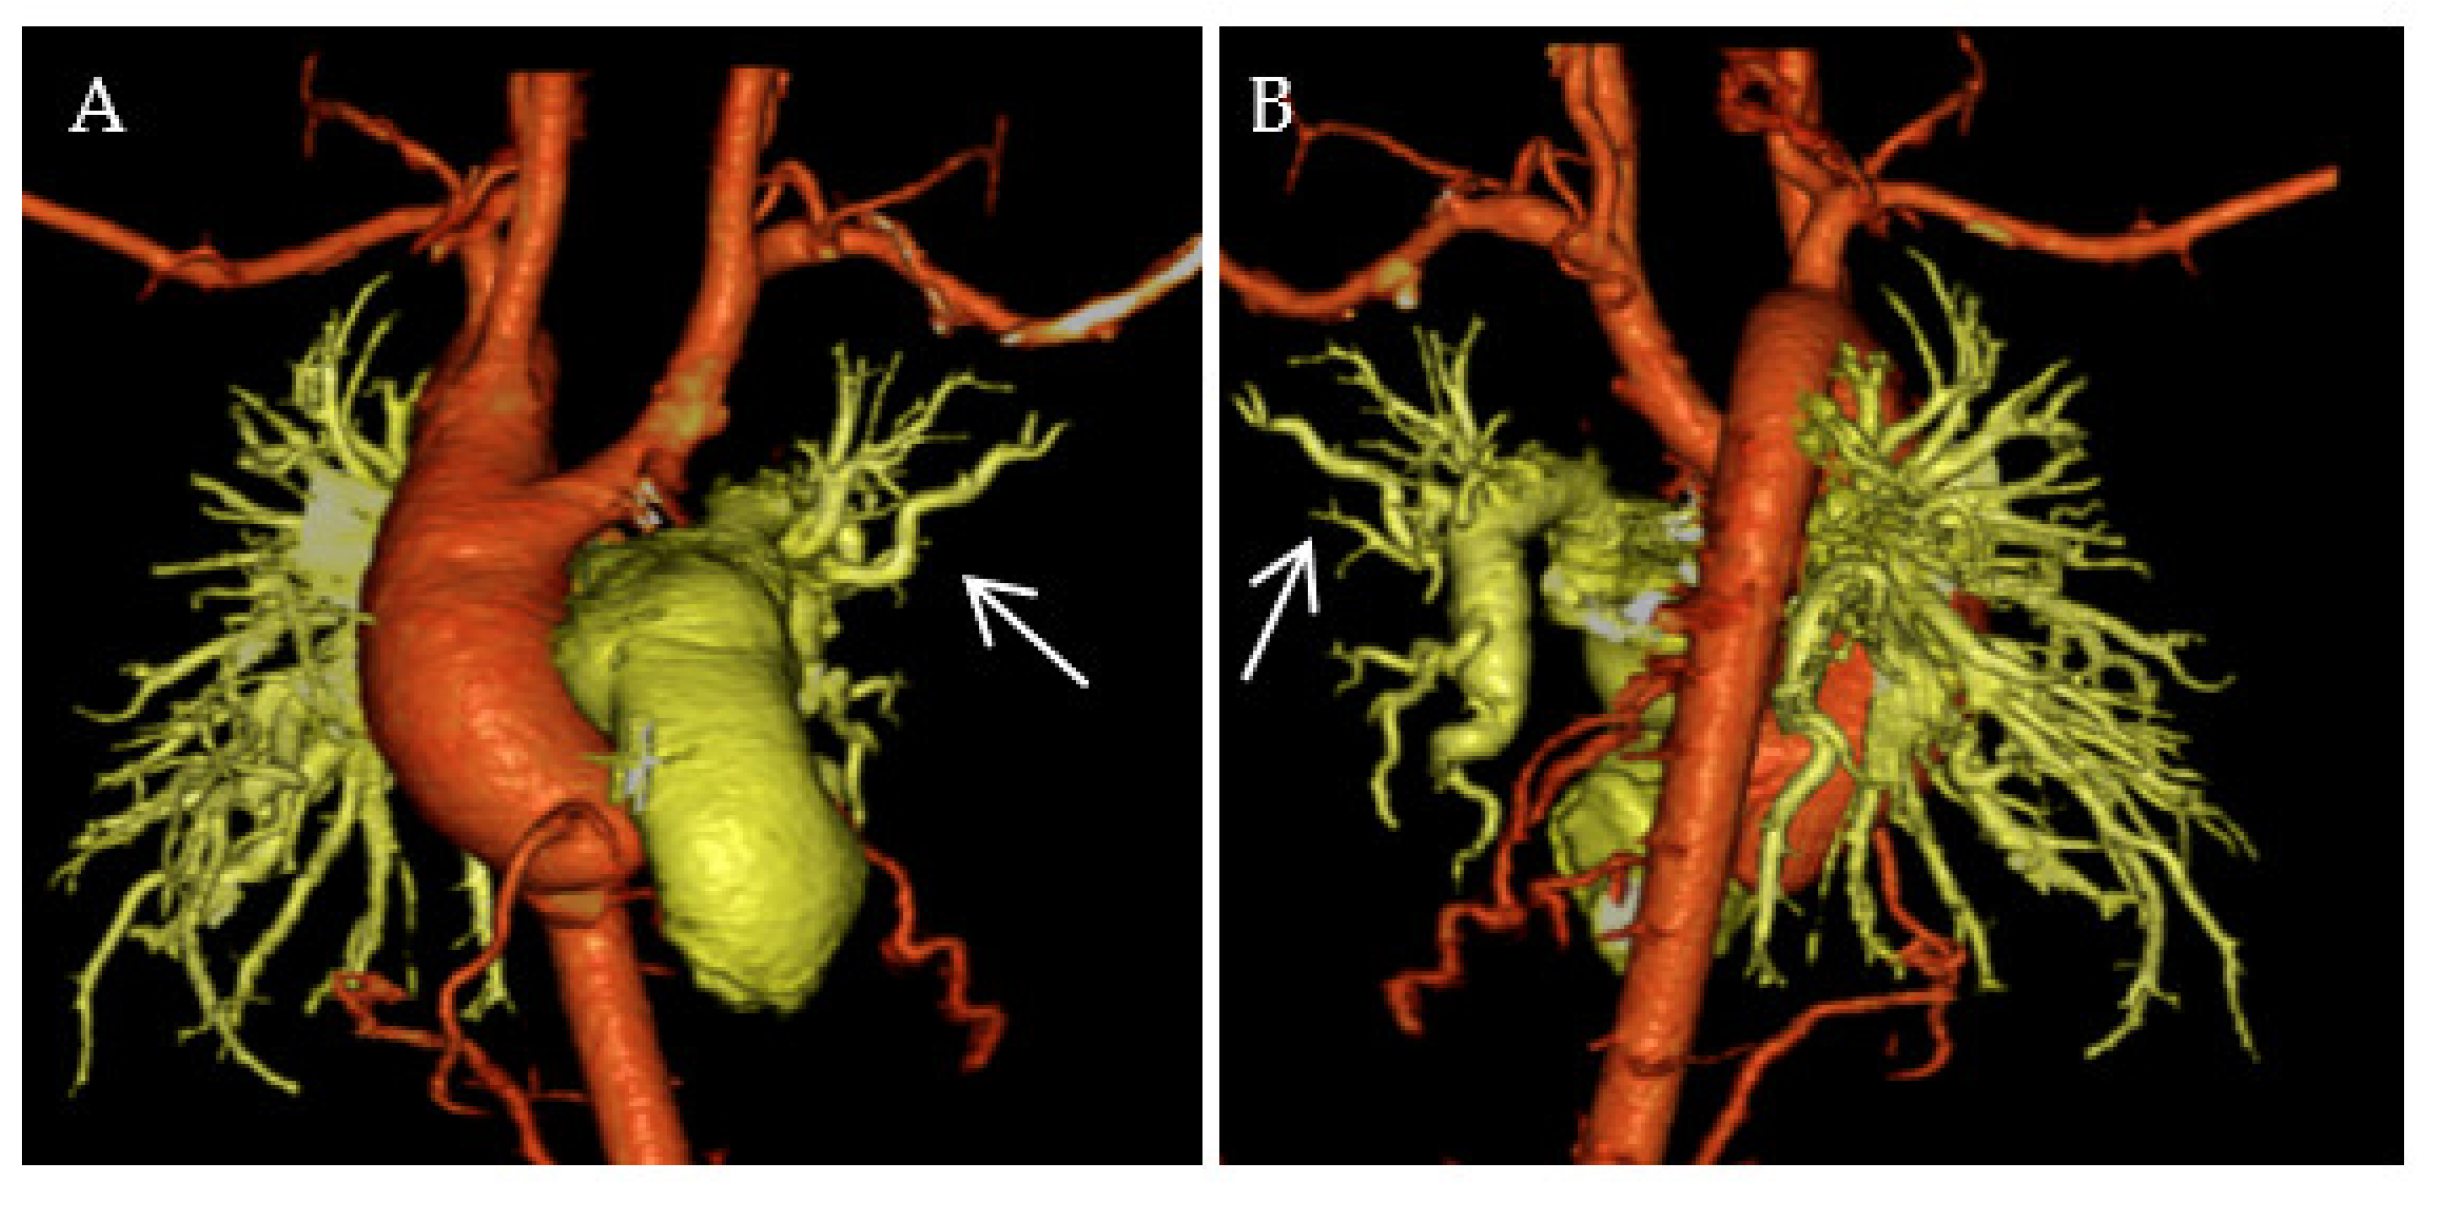

2.2. Segmental PH Associated with MAPCAs

2.3. Surgical Treatment for MAPCAs to Avoid Segmental PH